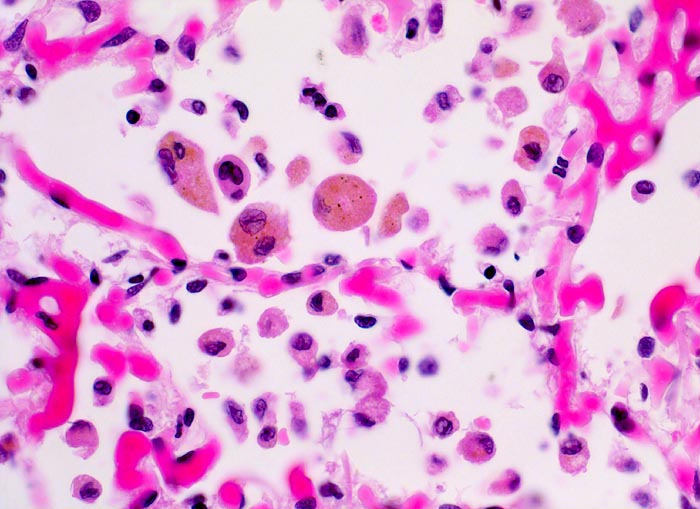

chronische Lungenstauung: Herzfehlerzellen

vaskulär / Durchblutungsstörung

Lunge

Die Kapillaren in den Alveolarsepten sind prall mit Blut gefüllt (Stauung). Bei sehr starker Stauung kann ein Teil des Blutes in die Alveolarräume übertreten und wird dort von den Alveolarmakrophagen phagozytiert. Deren Zytoplasma ist mit braungelbem Hämosiderin gefüllt. Daneben finden sich auch kleinere Makrophagen mit reichlich fein vakuolisiertem Zytoplasma.

Patient mit koronarer Herzkrankheit und Linksherzinsuffizienz.

400